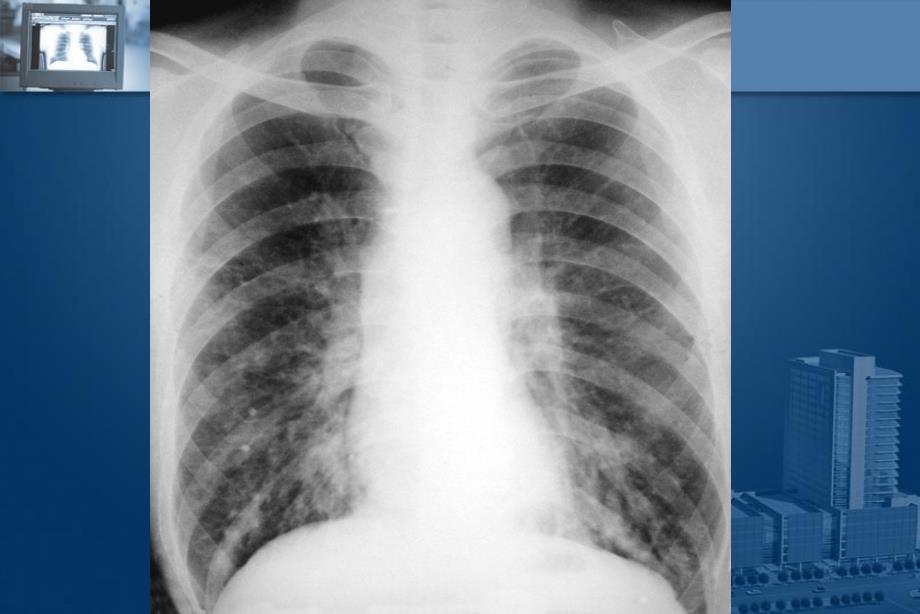

5、发病灶 淋巴管炎淋巴管炎 肺门淋巴结炎肺门淋巴结炎 X线表现线表现n肺内原发病灶表现为急性渗出性实变,呈边界模糊,肺内原发病灶表现为急性渗出性实变,呈边界模糊,云絮状影云絮状影n淋巴管炎呈条索状致密影淋巴管炎呈条索状致密影n肺门及纵隔淋巴结肿大肺门及纵隔淋巴结肿大急性粟粒性肺结核急性粟粒性肺结核 大量结核菌一次或短期内数次经血行达肺大量结核菌一次或短期内数次经血行达肺 X线表现线表现n两肺分布、大小、密度均匀相等粟粒状阴影(直径两肺分布、大小、密度均匀相等粟粒状阴影(直径 1.52毫米)毫米)n数月内可吸收,也可融合、干酪样化数月内可吸收,也可融合、干酪样化 慢性血行播散型肺结核慢性血行播散型

6、肺结核 结核菌在较长时间内多次侵入肺,病灶新老杂陈结核菌在较长时间内多次侵入肺,病灶新老杂陈X线表现线表现n大小不一,密度不同,分布不均的粟粒或结节,大小不一,密度不同,分布不均的粟粒或结节,n病灶以增殖为主,但与渗出、纤维、钙化灶并存病灶以增殖为主,但与渗出、纤维、钙化灶并存 继发性肺结核继发性肺结核 成年人结核最常见类型成年人结核最常见类型 X线表现线表现n病变局限于肺的一部,病变局限于肺的一部,多在肺尖多在肺尖n病灶以渗出为主,可伴有增殖,纤维、空洞等病灶病灶以渗出为主,可伴有增殖,纤维、空洞等病灶n结核球,干酪性肺炎结核球,干酪性肺炎为两特殊类型为两特殊类型 肺结核的肺结核的CT表现表